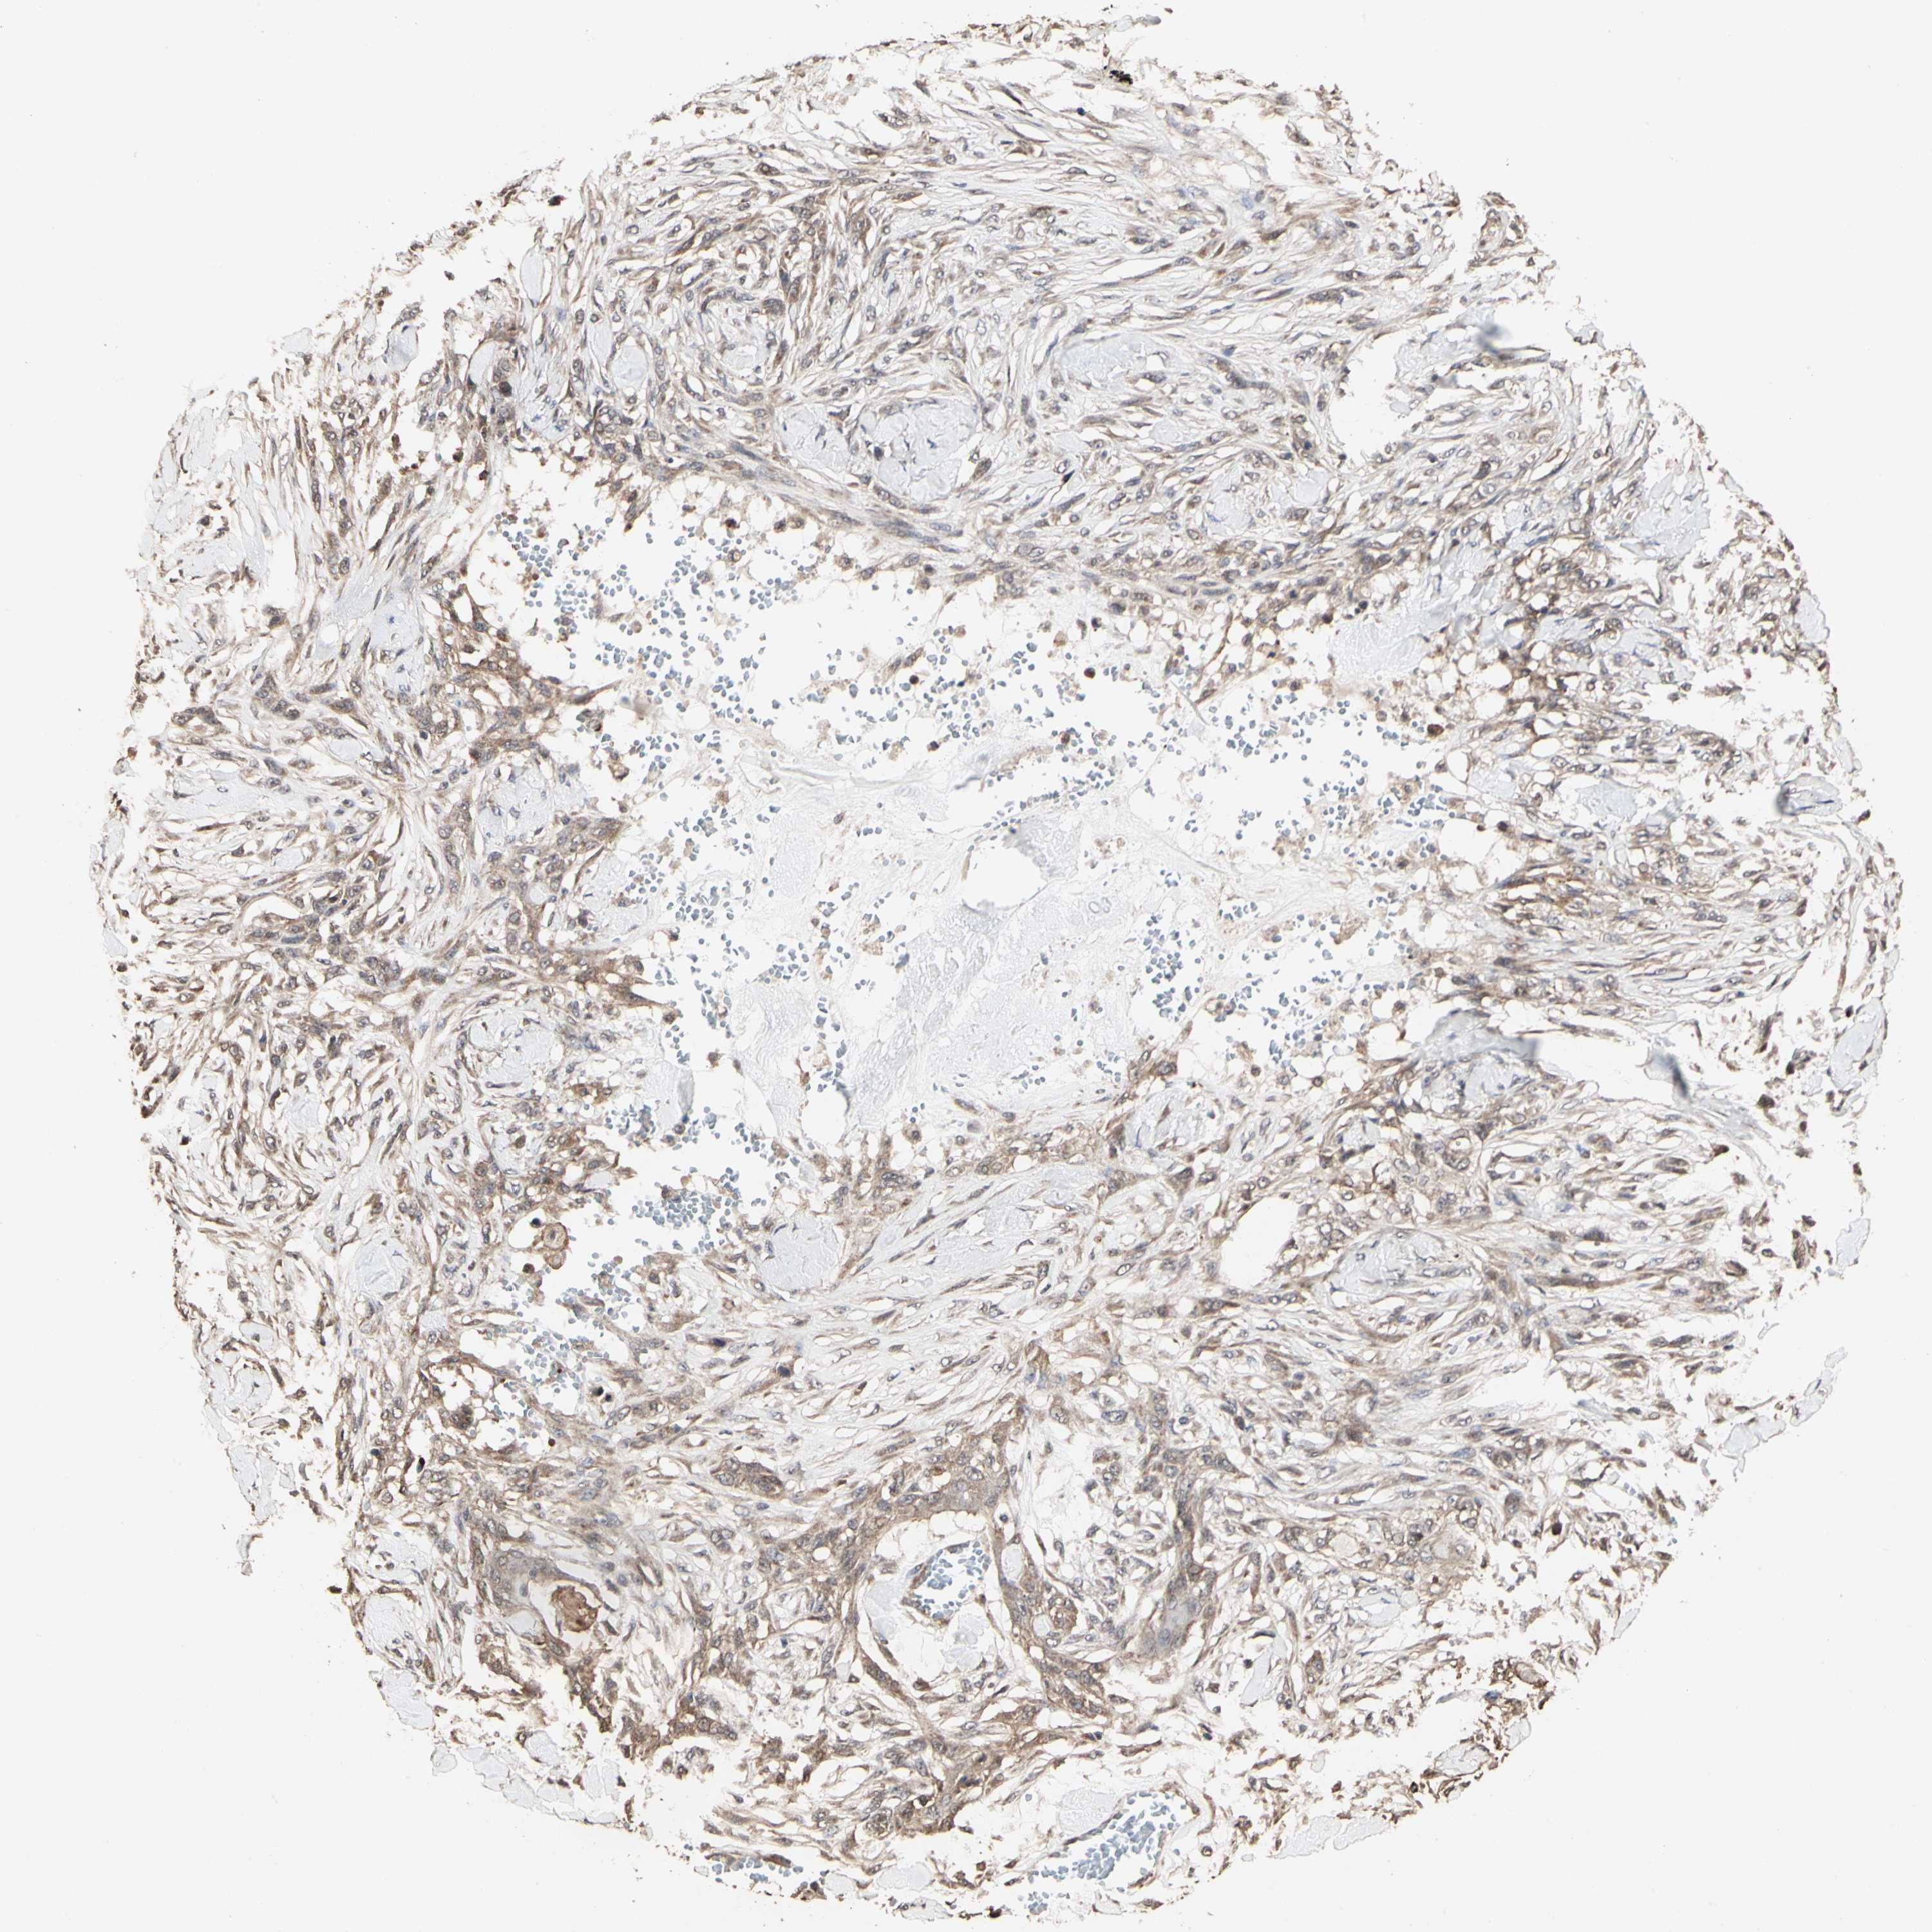

SKIN CANCER - Protein expressioni

A mouse-over function shows sample information and annotation data. Click on an image to view it in a full screen mode. Samples can be filtered based on level of antibody staining by selecting one or several of the following categories: high, medium, low and not detected. The assay and annotation is described here.

Antibody stainingi

Antibody staining in the annotated cell types in the current human tissue is reported as not detected, low, medium, or high, based on conventional immunohistochemistry profiling in selected tissues. This score is based on the combination of the staining intensity and fraction of stained cells.

Each image is clickable and will lead to virtual microscopy that enables deeper exploration of all samples and also displays staining intensity scores, fraction scores and subcellular localization as well as patient and tissue information for each sample.

Antibody HPA007669

Staining

High

Medium

Low

Not detected

Intensity

Strong

Moderate

Weak

Negative

Quantity

>75%

75%-25%

<25%

None

Location

Nuclear

Cytoplasmic/membranous

Cytoplasmic/membranous,nuclear

Squamous cell carcinoma, NOS

Basal cell carcinoma